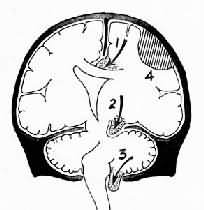

图16-6 脑疝模式图 1.扣带回疝;2.海马钩回疝;3.小脑扁桃体疝;4.硬膜外血肿 2.小脑天幕疝又称海马钩回疝。位于小脑天幕以上的额叶或颞叶内侧的肿瘤、出血、梗死等病变引起脑组织体积肿大,导致颞叶的海马钩回经小脑天幕孔向下膨出。海马钩回疝可导致以下后果:①同侧动眼神经在穿过小脑天幕裂孔处受压,引起同侧瞳孔一过性缩小,继之散大固定,及同侧眼上视和内视障碍。②中脑及脑干受压后移,可导致意识丧失;导水管变狭,脑脊液循环受阻加剧颅内压的升高;血管牵伸过度,引起中脑和桥脑上部出血梗死,可导致昏迷死亡。③中脑侧移,使对侧中脑的大脑脚抵压于该侧小脑天幕锐利的游离缘上,形成Kernohan切迹。严重时该处脑组织(含锥体索)出血坏死,导致与天幕上原发病变同侧的肢体瘫痪,引起假定位症。④压迫大脑后动脉引起同侧枕叶距状裂脑组织出血性梗死(图16-7)。

图16-7 海马钩回疝 左海马回内侧肿胀有深切迹(箭头),中脑右移变形,中脑右大脑脚受压,局部坏死出血(Kemohan切迹) 3.小脑扁桃体疝又称枕骨大孔疝。主要由于颅内高压或后颅凹占位性病变将小脑和延髓推向枕骨大孔并向下移位而形成小脑扁桃体疝。疝入枕骨大孔的小脑扁桃体和延髓成圆锥形,其腹侧出现枕骨大孔压迹(图16-8),由于延髓受压,生命中枢及网状结构受损,严重时可引起呼吸变慢甚至骤停,接着心脏停搏而猝死。